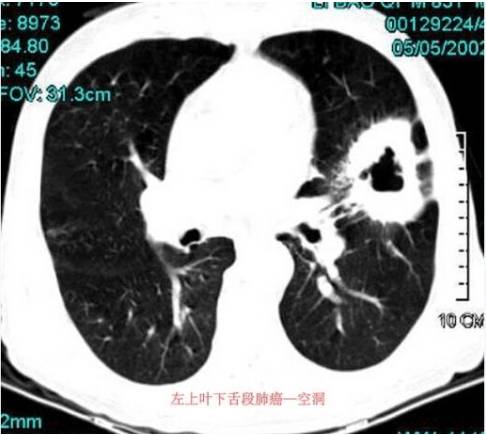

2.癌性空洞:多偏心形,内壁凹凸不平,无间隔,壁可厚薄不同,分叶,并常见外壁多为短毛刺并有兔耳征和(或)胸膜凹陷征,同时癌块在直径2 cm以下者很少见及有空洞的发生。

1.周围型支气管肺癌:周围型肺癌的空洞发生率为2%~16%,其中:鳞状细胞癌占80%,腺癌和大细胞癌占20%,支气管肺泡癌可发生空洞或薄壁囊性病变,单发或多发。小细胞未分化癌一般不发生空洞。

1. 空洞病变的大小:2cm 以下结节发生空洞以肺结核多见,肺癌在2cm以下较少发生空洞。4cm以上的肿块发生空洞多见于肺癌。有的肺结核空洞如纤维厚壁空洞和纤维干酪空洞也较大,前者形态不规则,后者有的与肺癌鉴别困难,需结合临床及实验室检查。慢性肺脓肿空洞可较大或较小。煤工尘肺空洞病灶较大。

2.空洞壁的厚度:一般将洞壁厚3mm以上称为厚壁空洞,<3mm薄壁空洞。厚壁空洞的疾病较多,常见于肺癌、肺结核的纤维干酪空洞、干酪空洞和纤维厚壁空洞,以及急性及慢性肺脓肿。薄壁空洞见于肺结核的浸润干酪灶空洞和纤维薄壁空洞。空洞壁薄厚不均见于肺癌和肺结核,明显的厚度不均匀使空洞为偏心性或特殊形态。 肺癌空洞的壁一般在肺门侧较厚,空洞多偏于外侧。结核球在引流支气管开口处的干酪病变最先软化,因此空洞腔开始多位于病变的肺门侧,即与引流支气管相连处,呈小圆形。空洞进一步发展呈新月状,也多位于病变的肺门侧,最后可形成类圆形空洞。霉菌引起的空洞根据病原菌种类不同可为厚壁、薄壁或厚薄不均。 3.空洞的内缘:内缘光滑见于肺脓肿、肺结核纤维空洞;内缘毛糙见于肺脓肿、肺结核的纤维干酪空洞;空洞内缘凹凸不平见于肺癌和肺结核纤维干酪空洞;空洞内缘的壁结节主要发生于肺癌,肺结核纤维干酪空洞内的未液化的干酪物质也可以形成壁结节。

4.空洞的外缘:空洞外缘清楚者见于肺结核纤维干酪空洞、慢性肺脓肿,有的肺癌空洞的外缘也光滑清楚。外缘有毛刺及“ 放射冠”影像者见于肺结核的纤维厚壁空洞和肺癌。外缘有分叶者多见于肺癌。